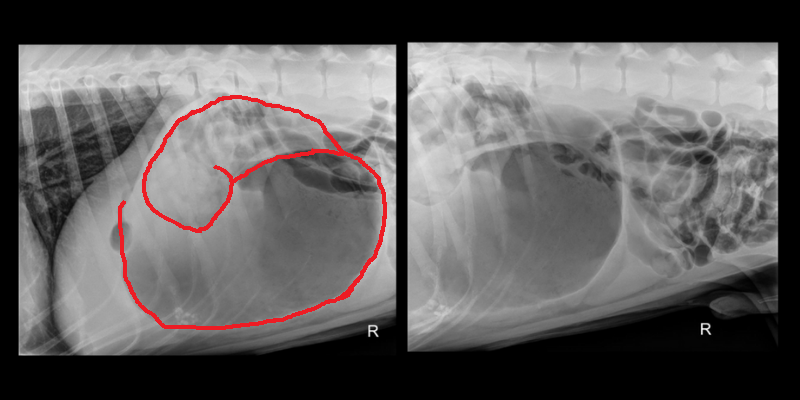

The best way to diagnose GDV is with abdominal x-rays, and that diagnosis must be made before many other life-saving measures can be taken Our team rushed into action so that Dante’s wait for those treatments would be minimized. Fortunately, it does not take long to interpret the classic “double bubble” or “Popeye’s arm” appearance of the stomach when it has flipped over on itself (see x-rays below). Dante’s radiographs provided a definitive diagnosis of GDV.

With this confirmation, there are only two options: emergency surgery or humane euthanasia. Returning home without treatment is not an option because dogs cannot survive GDV without treatment, and the pet would suffer a very painful death. With emergency surgery, dogs stand an 80% chance of survival, but there is still no time to waste.

The red outlines the “Double Bubble” or “Popeye’s Arm” appearance of the stomach on Dante’s x-ray.